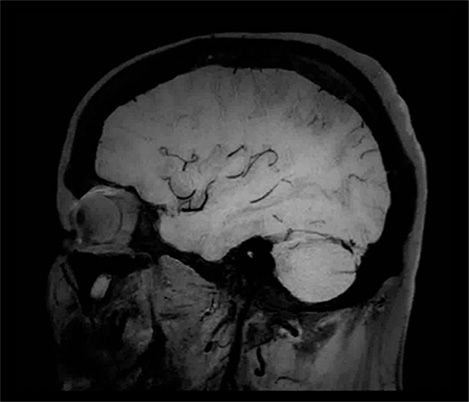

Klinische Fallbeispiele für nahezu jede anatomische Struktur Sehen Sie sich mehr als 100 klinische Fallbeispiele von Kollegen auf der ganzen Welt an, die zeigen, wie die digitale MR-Technologie von Philips Ihre Anforderungen in der Bildverarbeitung unterstützt.